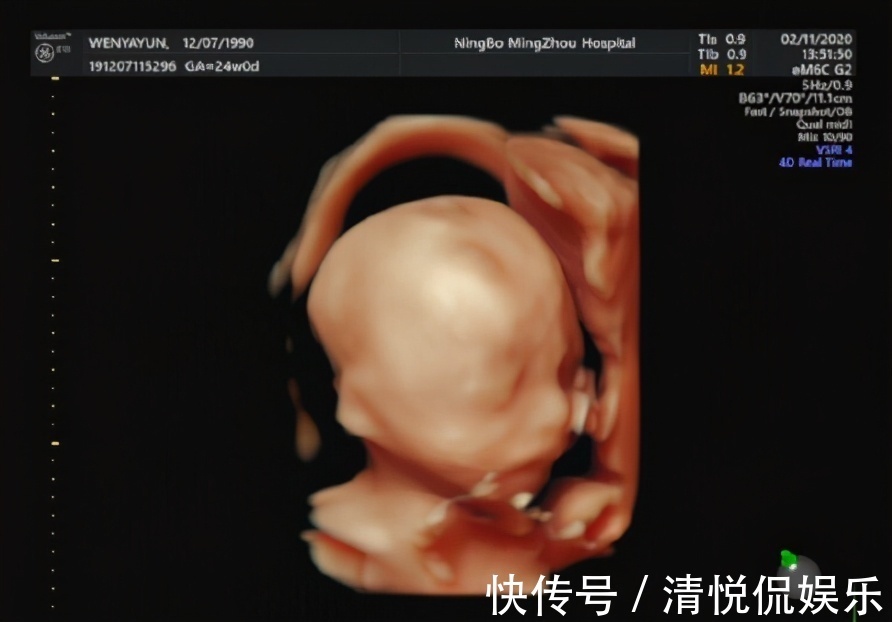

第三次:20-28周产检?这个孕周段有个重要的产检,叫“排畸B超”。有的医院是做普通B超进行排畸,有的医院是做四维排畸。有的医院做一次排畸B超,在孕20-24周做,有的医院做两次排畸B超,孕20-24周做一次,到了孕28周会再做一次。具体,怎么查、查几次,就看孕妈自己产检医院的安排就好了,一般医生会提前告知。因为 这1-2次B超都是排查胎儿的重大畸形,准爸爸就更不能缺席了,一定要陪在孕妈身边。有的医院检查时,准爸爸是可以陪着进去的,那检查时,医生会告诉准爸妈胎儿的各个身体部位,那准爸爸就更不要错过和胎宝宝的第一次见面啦!

? 做排畸B超,孕妈需要提前了解几点:① 普通B超(三维)也完全可以起到排畸的效果,只是四维B超可以算是宝宝的第一张照片,比较有意义;② 就算排畸B超顺利通过,胎儿出生后也还可能存在畸形,毕竟B超也不是万能的,这些准爸妈要正确认识;③ 检查时孕妈要心态平和,避免过分紧张,不然会影响胎宝宝的面部表情成像;如果检查一次没看清楚,医生建议复查,也不要太紧张,配合医生检查就好,一般都能顺利通过。